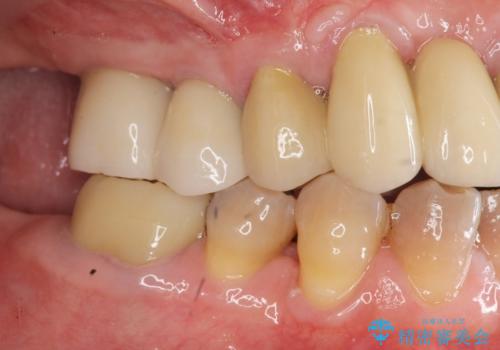

- 他院で上顎は全て抜歯し、入れ歯にする必要があると言われ相談に来院されました。

検査の結果、重度の歯周病であることから保存が難しい歯は抜歯を行いインプラントを、残すことが可能な歯には再生治療を含めた歯周病治療を行いより多くの歯を残す歯周病治療を計画します。

上顎は、残っている前歯も揺れがあり残すためにはクラウンでつなぐ歯周補綴が必要な状態です。

また咬合負担に不安のある前歯を助けるためにも、臼歯部にインプラント補綴を行いしっかりとかめる状態とすることも大切です。